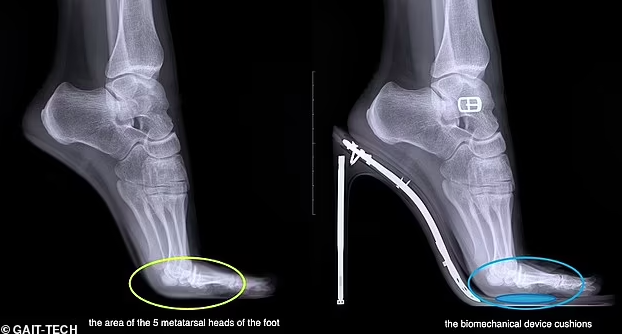

Итальянская компания GAIT-TECH разработала "умную" стельку для обуви на высокой платформе, которая снижает риск для здоровья и перераспределяет давление по всей стопе.

По данным журналистов, "умная" стелька от итальянских разработчиков из GAIT-TECH амортизирует удары при ходьбе и перераспределяет давление по стопе. Ее встраивают еще на стадии изготовления обуви, поэтому ее не видно при использовании.

Стелька была создана, чтобы перераспределить повышенную нагрузку между головками плюсневых костей, сделав работу 1-й и 5-й плюсневых костей более эффективной, а также снизив давление нагрузки над остальными тремя.